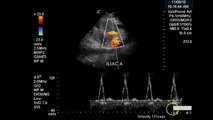

Disclaimer: The medical information contained herein is intended for physician medical licensing exam review purposes only, and are not intended for diagnosis .\r